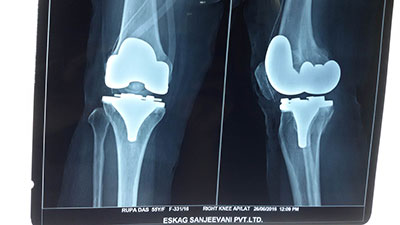

Case 7: Total Knee Replacement

54 years female was suffering from both knee pain for last 4-5 years. She had bilateral advanced osteoarthritis knee.

Patient underwent knee replacement surgery in two stages. 1st right knee was replaced after 8 months left knee was replaced.

X-RAY 2

post op xray after knee replacement